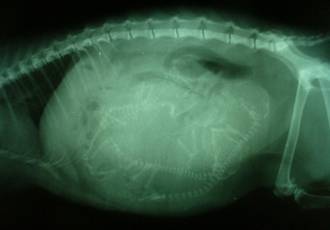

Определить беременность кошки какими-либо тестами в настоящее время не представляется возможным. Наличие беременности в особых случаях можно установить с помощью УЗИ, начиная примерно с 15-го дня после покрытия. Опытный врач также сможет определить беременность примерно на 20-ый день после покрытия при помощи пальпации, но не позже, так как матка заполнится жидкостью и нащупать плоды можно будет уже только на сроке в 49-55 дней

Примерно на шестой неделе беременности, если формируется более одного или двух котят, живот кошки вдруг становится сразу очень большим, явно больше, чем до этого: на этой стадии рост эмбрионов происходит быстро, и они не прощупываются по отдельности. После седьмой недели уже можно ощутить движение котят и прощупывать их головки. К этому времени кошка становится беспокойной, ищет место, в котором можно было бы устроить гнездо.